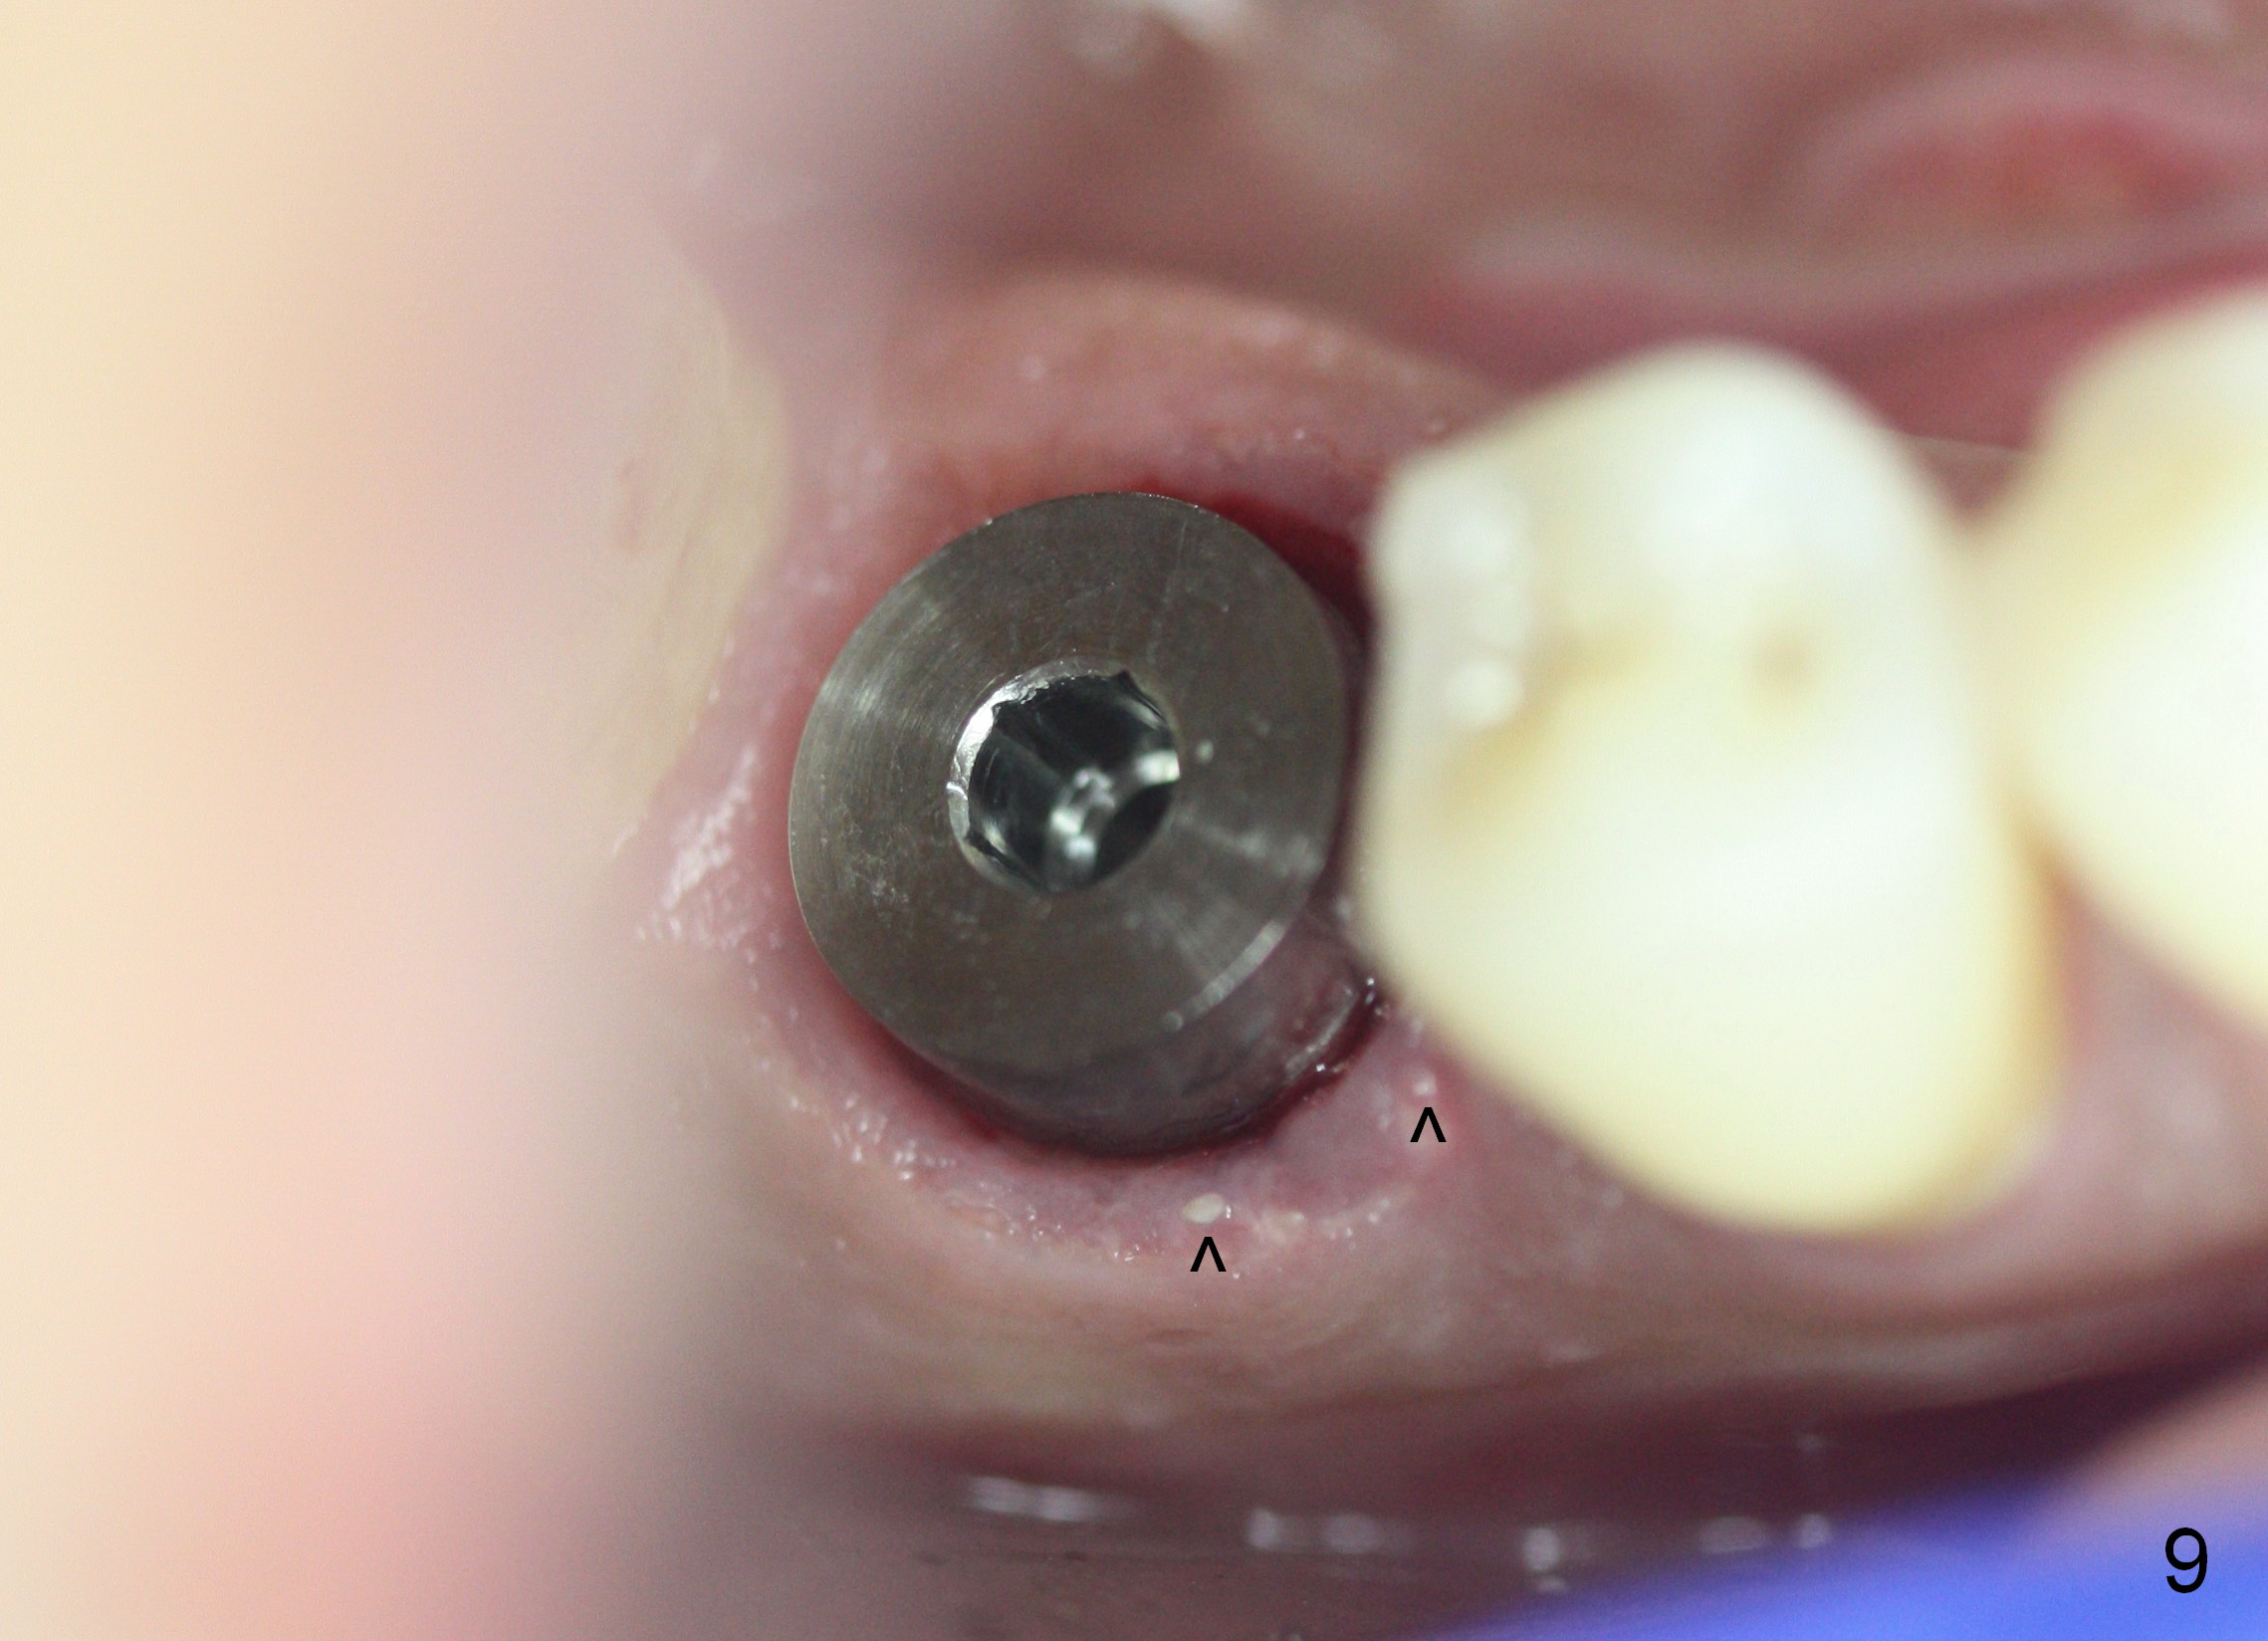

The next time the patient returns is 8.5 months postop (Fig.8,9). When an immediate provisional is not provided, the patient tends not to return early. In fact, retention of an immediate provisional and confidence in it by the patient promotes early finish of treatment (permanent crown).